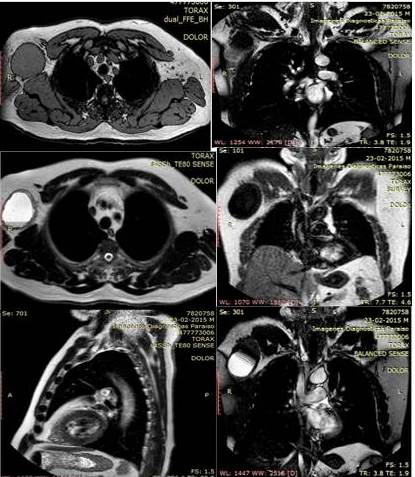

Exámenes de laboratorio clínico dentro de parámetros normales. Por el cual se ordenan exploraciones complementarias, donde se destaca en la resonancia magnética nuclear de tórax (RM) técnica a predominio de T1, T2 revelan la presencia de lesión ocupante de espacio ovalada de 7,3 cm x 6,2 cm x 10 cm en región axilar medial derecha, discretamente hiperintensa al músculo en T1, doble señal en secuencia T2 y supresión de grasa en relación a alto contenido proteico-material purulenta. Presencia de pared gruesa con deformidad de la superficie cutánea sin embargo, no hay edema significativo de los tejidos blandos perilesionales lo que impresiona como diagnóstico a considerar adenopatía abscedada vs., neoplasia primaria con degeneración quística y hemorragia intra-lesional (Figura 1).

En los estudios de imágenes son inespecíficos, no existen rasgos desde el punto de visto radiológicos tanto en la tomografía computada (TC) y en la resonancia magnética (RM), que sean definitivos y que diferencien al MFSbBG de otro tipo de fibrosarcomas, ya que se comportan como masas sólidas con grados variables de realce, necrosis o degeneración quística y hemorrágica. En las imágenes de TC sin contraste el componente fibroso de estos tumores ha sido descrito como isodensa al tejido muscular y el componente mixoide como hipodenso. Por otro lado, en la RM, el componente fibroso se caracteriza como hipointensa en T1; y el coeficiente de atenuación, la intensidad de señal en T2 y el patrón de captación varían en función del componente mixoide (11,12,13). Como sucedió con caso en estudio.